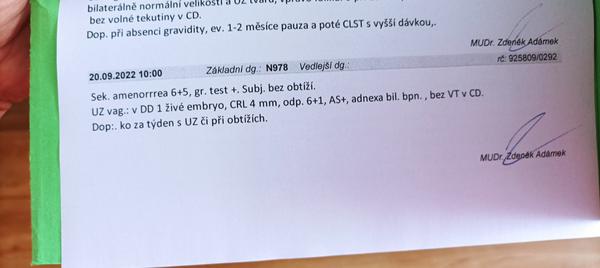

Holky první kontrola 6+1 se srdíčkem ale bez akce

Kontrola druhá bude 7+1 myslíte že už budete tlouct ❤️ potřebuji utěšit mám nervy